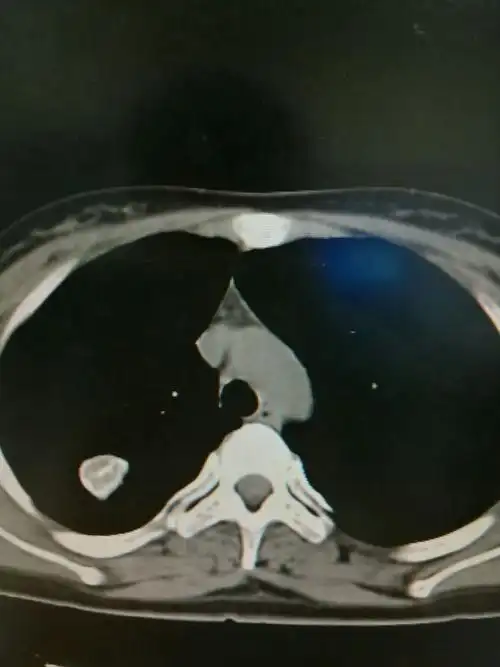

两肺散在实性肺结节,右肺胸膜下结核球

其它 结核球的相关征象及诊断 写美篇右肺上叶见类圆形混杂密度影,内

其中80%为良性包括:災性假瘤,错构瘤,结核球,真菌感染,硬化性肺细胞瘤

肺结核球肺结核结核球